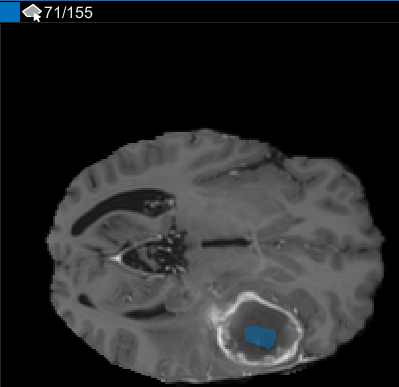

После использования интерполяции проверяйте отдельные срезы, чтобы видеть, создала ли интерполяция удовлетворительные ROI. Обратите внимание на то, что ROI на срезе 71 не заполняет целый объект, который вы хотите сегментировать. Можно вручную настроить ROI с помощью инструмента Paint Brush. В качестве альтернативы можно использовать один из инструментов на вкладке Automate. Например, можно использовать Активные Контуры, чтобы вырастить ROI на срезах, где это не заполняет полный размер опухоли. Можно также использовать Добавить Алгоритм, чтобы задать собственный алгоритм, чтобы работать с ROI.